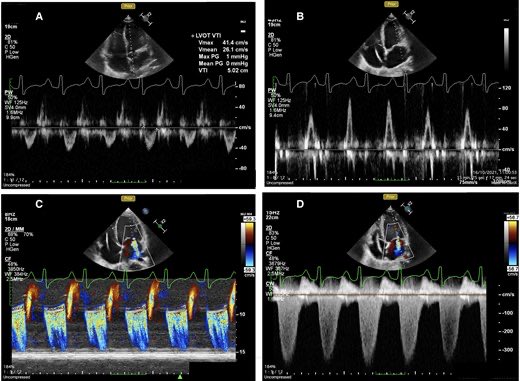

Diastolic dysfunction: a comparison of 2025 ASE, 2024 BSE and 2022 EACVI guidelines The 2025 ASE guidelines provide a comprehensive framework for the assessment of diastolic dysfunction, integrating a clearly defined stepwise algorithm with a global approach that incorporates

Diastolic dysfunction: a comparison of 2025 ASE, 2024 BSE and 2022 EACVI guidelines

The 2025 ASE guidelines provide a comprehensive framework for the assessment of diastolic dysfunction, integrating a clearly defined stepwise algorithm with a global approach that incorporates